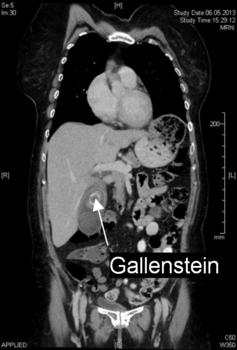

• Computertomographie (CT): Sollten die vorherigen Abklärungen nicht ausreichen bzw. weitere Fragestellungen im Raum stehen, kann eine Computertomographie durchgeführt werden. Mit einer CT können weitere Entzündungen (Divertikulitis) oder Krankheiten (wie z.B. Tumore) festgestellt werden.